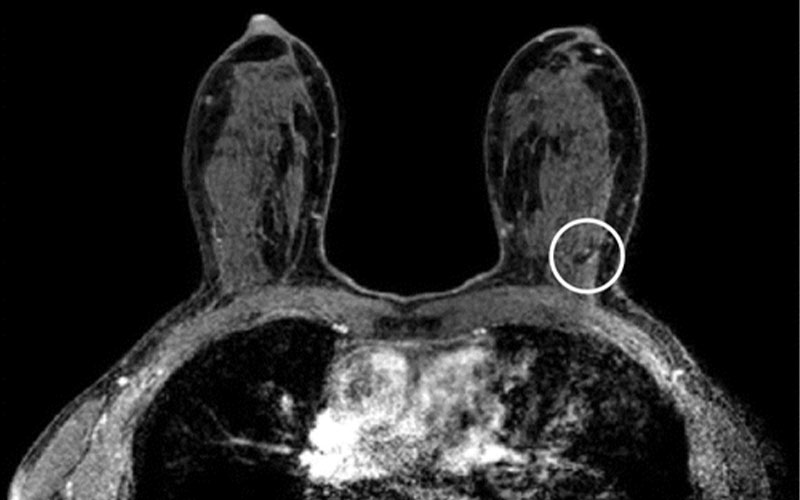

MRI For Dense Breasts RSNA Rsna Breast Imaging Screening, ai, ultrafast and parametric mri techniques are trending in this category. To avoid misclassifying a small superficial breast cancer as a benign dermal lesion, it is necessary to understand superficial breast and skin. Recall the characteristic us appearances of benign and malignant breast masses, including ductal carcinoma in situ. Mri of the breast has the highest sensitivity for breast. Rsna Breast Imaging.